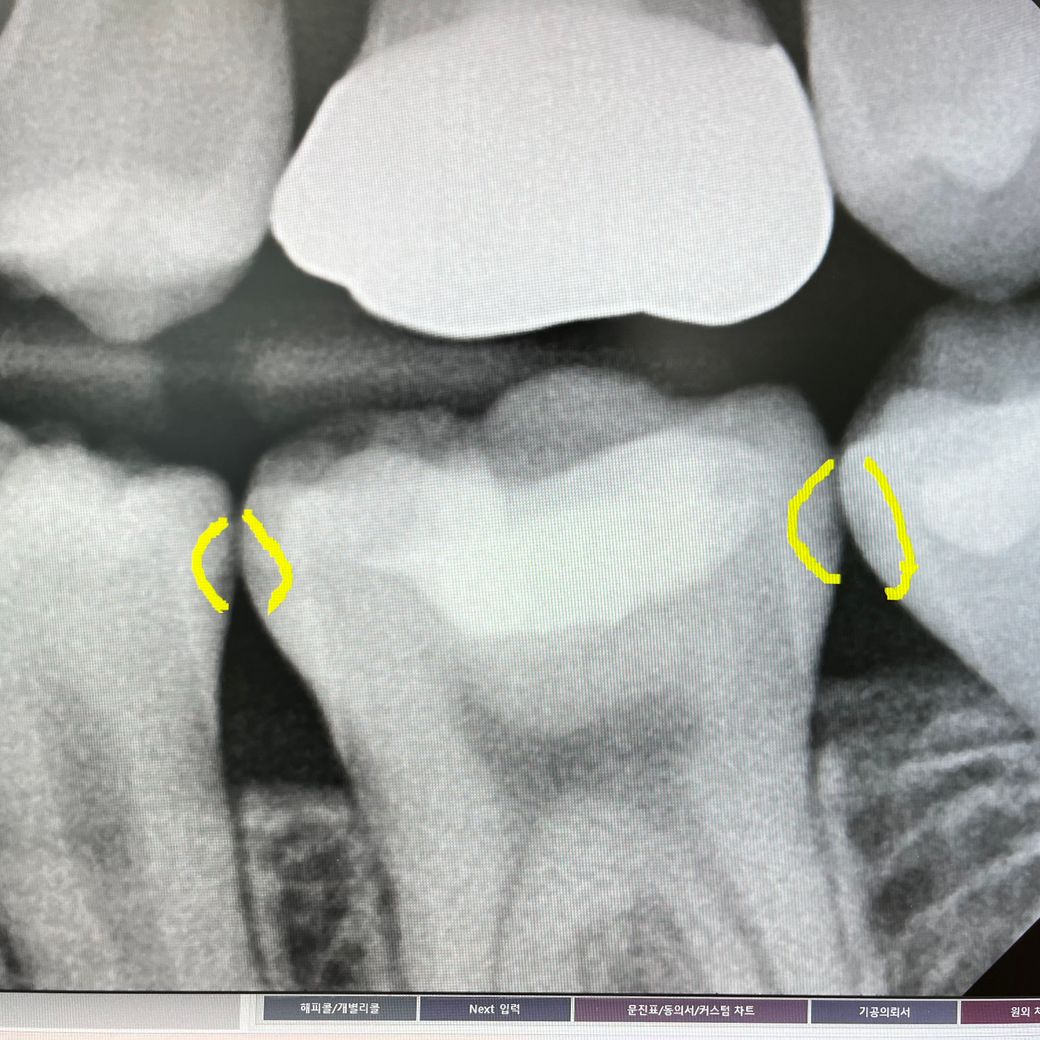

x-ray 사진으로 보았을 때는 인접면 충치 뿐만 아니라 교합면에도 어느정도 충치 및 손상이 있을 것으로 보입니다. 광범위한 수복이 있을 경우에는 레진으로 하는 것이 오히려 치아에 안 좋은 영향을 줄 수 있으므로 인레이 이상의 치료를 권하고 있습니다.

사진으로 보이는 충치는 진행이 많이 된것 같아 보이지는 않습니다.